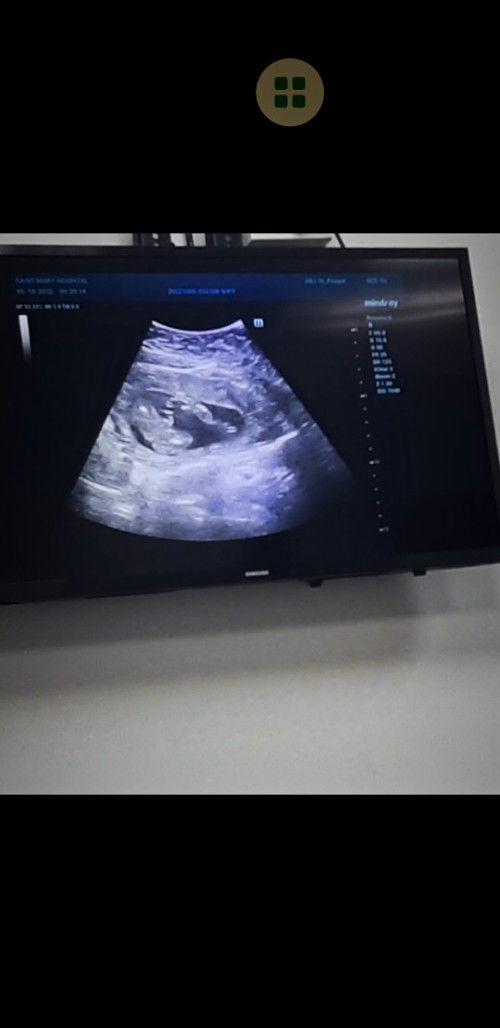

อายุครรภ์ 18w วันนี้ไปอัตราซาวด์มา แม่ๆว่าน้องเป็นผู้ชายหรือผู้หญิงคะ 😁😁🥰🥰😍😍#ขอบพระคุณทุกคอมเม้นท์ค่ะ

ลูกสาวหรือป่าวน้าา💗